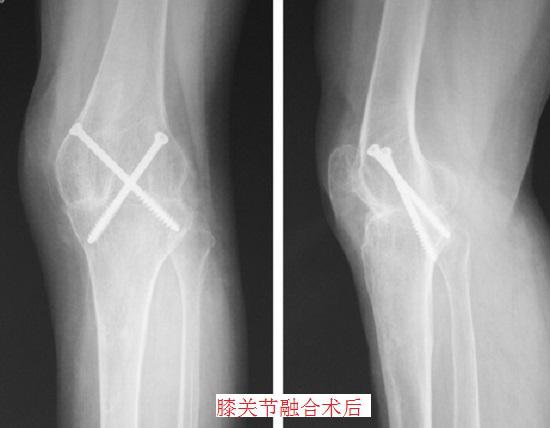

所谓关节融合术,是指让关节两端的骨骼通过骨面进行接触(骨面应具有活性;脊椎间的融合除外,大多数情况下直接固定即可),使骨骼间的骨质再生并连接、融合为一体,同时去除关节囊及无用组织、清除关节附近的病灶及隐患,使关节在功能位固定的一种外科手术。关节融合术的目的在于:对关节病变进行姑息性治疗,彻底消灭顽固性病灶,对残缺的主要功能进行舍弃,以换取更多次要功能。

就关节融合位置的不同,有膝关节融合、髋关节融合、踝关节融合、脊椎融合等类型,不同位置的关节融合术在细节方面具有不同的适应证和禁忌证,但总体来讲,关节融合术的实施应符合下列适应证,并排除相应禁忌证。